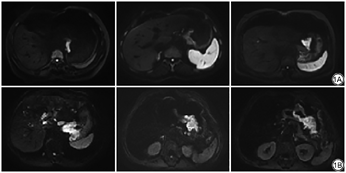

两组患者胃癌病灶呈T1WI低T2WI稍高信号,T2WI-SPIR呈高信号,DWI(b=1200 t)呈高信号。

两名资深主治医师的主观评分Kappa值为0.875,一致性良好。A、B两组图像的主观评分见表2,A组和B组间图像的主观评分差异有统计学意义(P<0.05),两组的IVIM-DWI(b=1200 t)图像见图1。